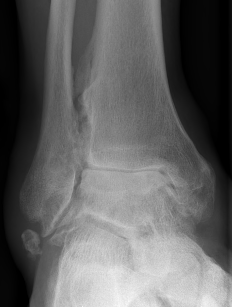

CT

Evaluate bone stock to determine if TAR is appropriate